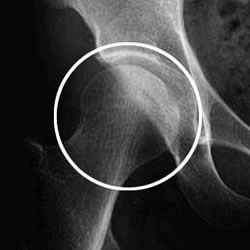

図1 正常な股関節![]() |

図1は正常な股関節の図です。高齢の方が転んだときに、股関節を打ったりひねったりして、大腿骨が骨折することがあります。骨折した場所により「頚部骨折」と「転子部骨折」に分かれます。